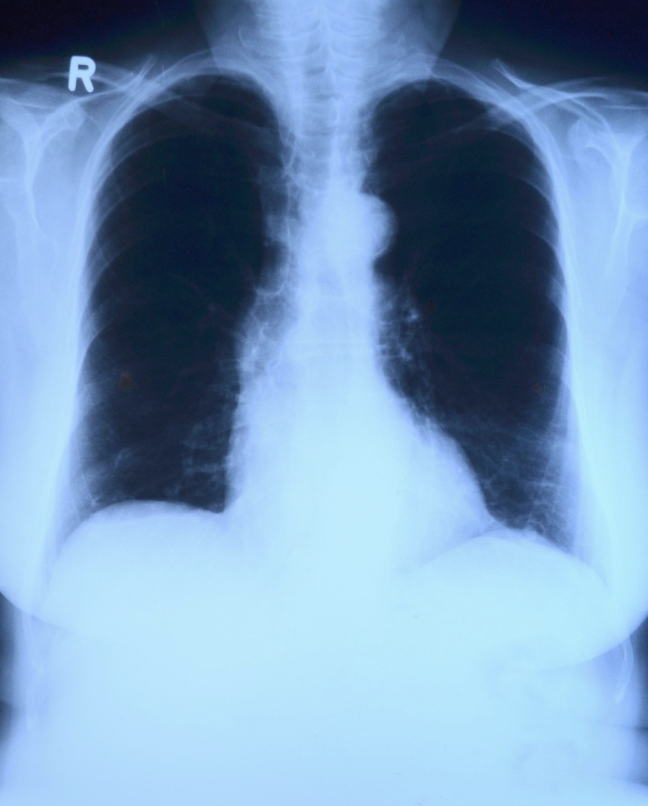

雪梨科技大學團隊進行的最新實驗顯示,即便空氣污染濃度被認定為「偏低」,這些直徑不到2.5微米的懸浮粒子,仍會在細胞層面引發顯著破壞。研究人員利用雄性小鼠及培養出的人類肺臟組織進行測試,模擬日常生活中常見的PM2.5接觸情境。

實驗結果令人振奮,當補充維生素C之後,肺部細胞呈現三大關鍵改善現象。首先,負責製造能量的粒線體損失情形大幅減輕;其次,因空氣污染引起的發炎現象受到抑制;最後,氧化壓力導致的細胞受損程度也顯著下降。

韋恩說明,維生素C之所以能發揮保護作用,關鍵在於它的抗氧化能力,可以中和空污產生的不穩定自由基,阻斷連鎖性的細胞功能損害。研究團隊認為,在實驗環境下,補充維生素C確實能減緩低劑量PM2.5帶來的負面衝擊,未來有望成為高危險群的輔助防護選項。